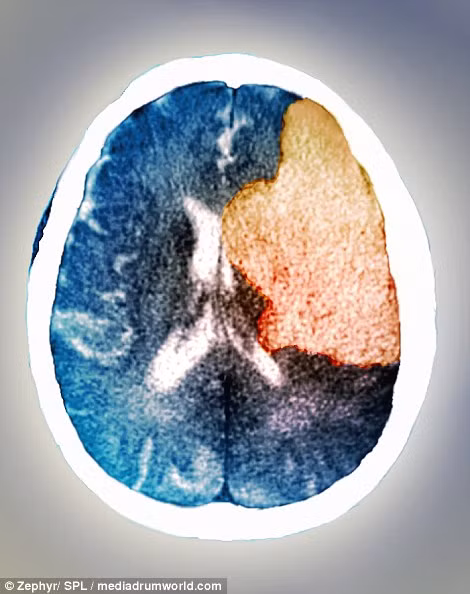

Đây là hình ảnh của não trong cơn đột quỵ. Ảnh chụp CT cho thấy vùng não bên phải của bệnh nhân đã bị liệt sau khi bị đột quỵ. Đột quỵ xảy ra khi lượng máu cung cấp cho một vùng não nào đó bị thiếu hoặc hoàn toàn không có khiến các tế bào não chết đi.